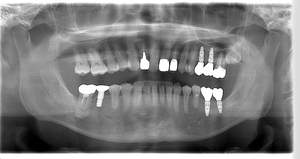

レントゲン写真

- Befor

- After

| 年齢 | 50代・男性 |

| 主訴 | 左上7番 左下5番7番 |

| 治療内容 | ・インプラント埋入 ※1:GBR(骨造成)・・・骨再生誘導法。骨の高さや厚みを人工骨や人工膜などを使用し再生する方法 |

| 治療費 | 合計:1,809,500円(税込) ■内訳 ・左上7番 ・左下5番7番 |

| 治療期間 | 左上7番約1年 左下5番7番約10ヵ月 |

| 治療方針 | 左上7番は昔他院で被せものをしており、被せものの中が歯ぐきの中まで虫歯になっていたため抜歯せざるを得ない状態だった。抜歯と同時に骨造成を行い、骨が出来るまで4ヵ月待ってからインプラントを埋入した。 ※2ポンティック・・・歯のない部分を補うダミーの歯。 |

| 担当者所見 | 元々金属の被せものが多く入っていたため、2次カリエス※3が多かった。今回は金属ではなく、ジルコニアを使用し、2次カリエスにならないよう、患者様にはブラッシング指導とメンテナンスの重要性をお伝えした。 ※3二次カリエス・・・詰め物や被せものを入れた歯が虫歯になること。 |